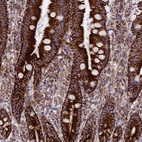

Immunohistochemical staining of human skeletal muscle shows strong granular cytoplasmic positivity in myocytes.